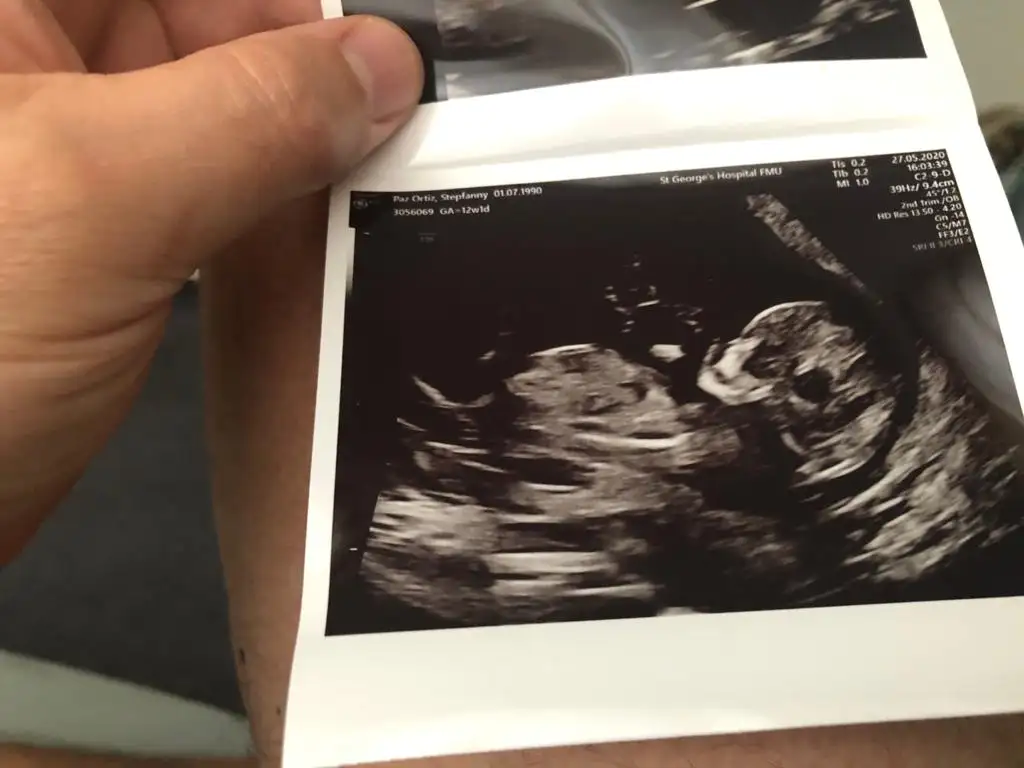

Rica etsem banada tahmin yaparmisiniz 8 haftada kiz demistiniz tekrar gondermemi istemistiniz dayanamadim bu usg 11 haftalik

Kız gibi net de değil kız sanki 12-13 olunca tekrar usg paylaşın